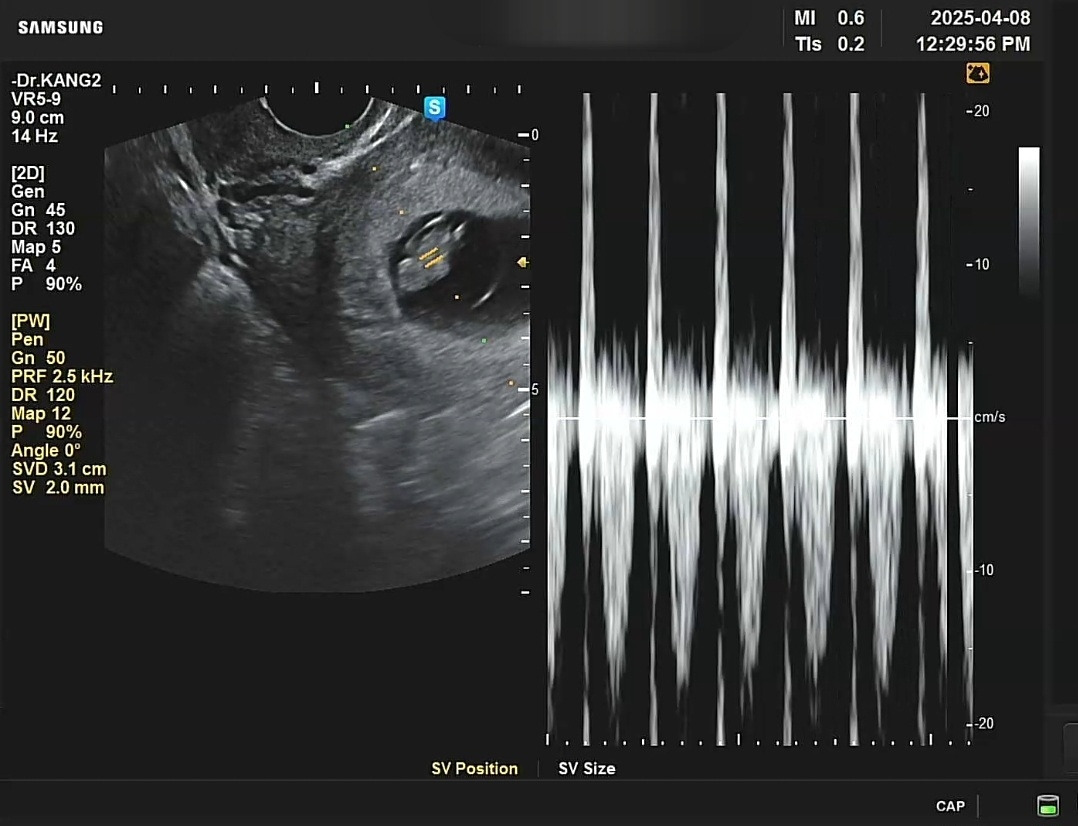

2주 만에 보고 온 초음파는 아주 경과가 좋았다. 아이는 무럭무럭 자라 젤리곰 크기가 되었다. 심장도 팔딱팔딱 뛰고 소리는 더 우렁차졌다. 팔다리가 생기는 중이란다. 8주 3일. 안팎으로 잘 크는 중. 엄마가 동행해 초음파를 함께 보곤 선생님께 나를 당부하며 펑펑 우셨다. 눈물포인트는 팔딱팔딱 뛰는 아가 심장.